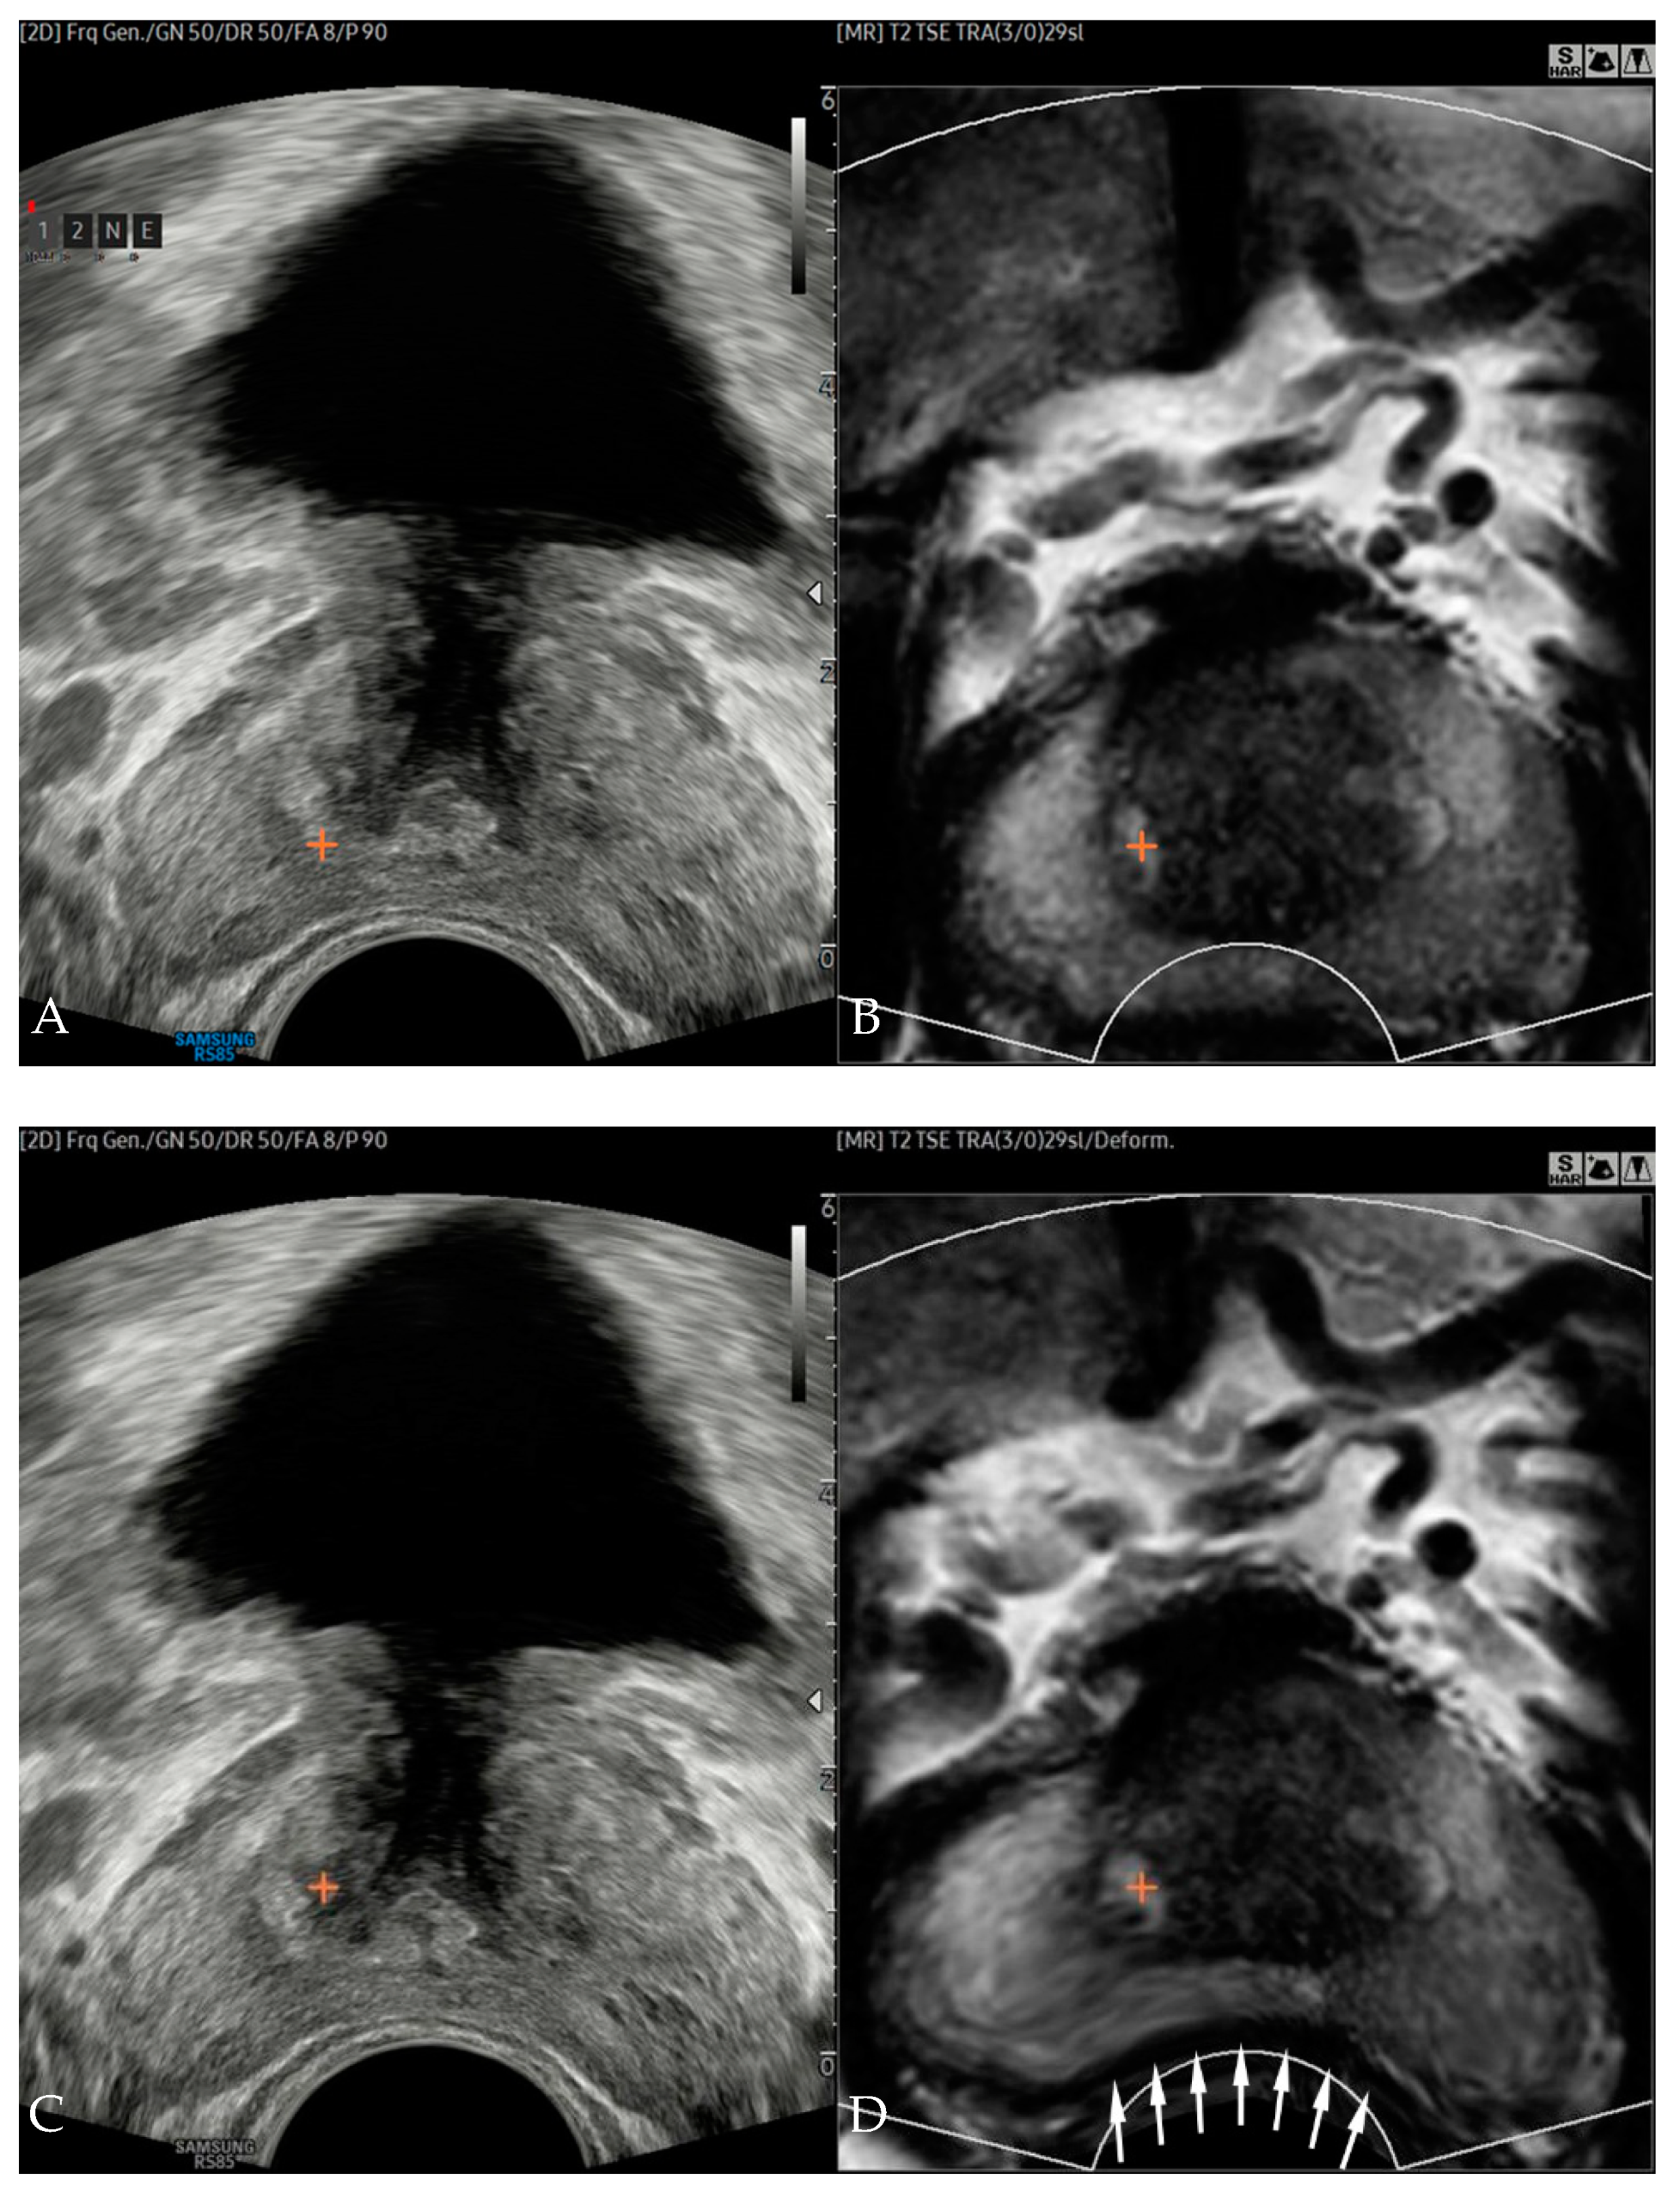

2.3. Image Fusion, Registration, and Error Measurements

2.4. Prostate Biopsy